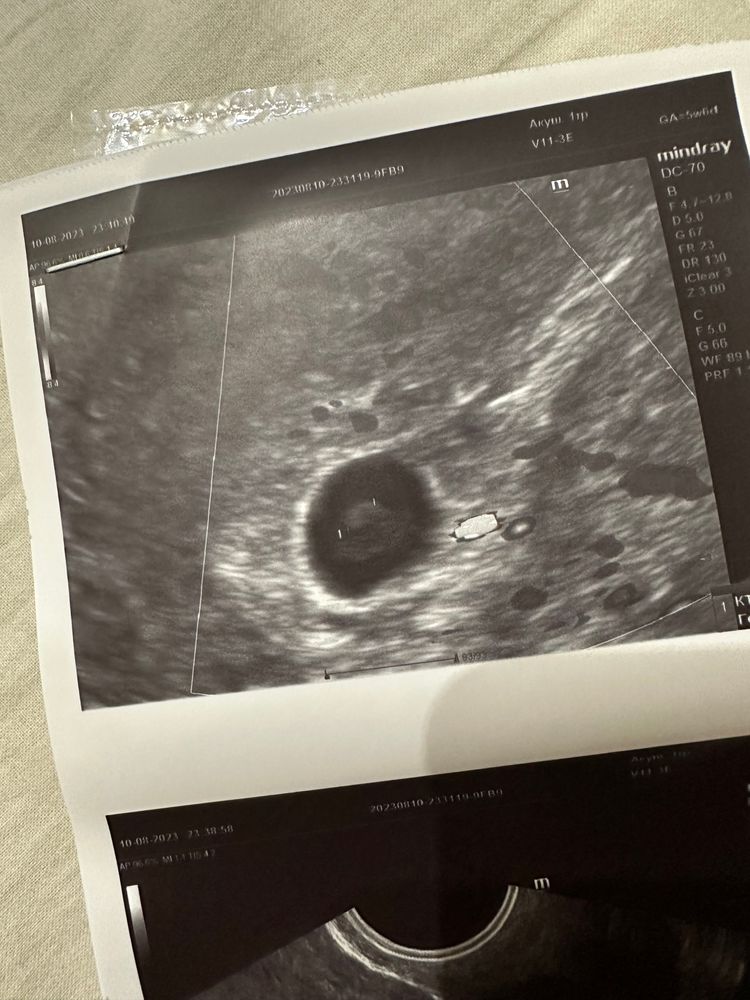

Ксения, спасибо . Сходила сделала в другом месте . Вот что увидели . Изображение Это же эмбрион ? Который вот вот разовьется

Сабрина, Изображение Изображение А вот узи сегодняшнее